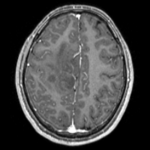

this is the fixed T2 reference image. All images are aligned into this space this is the fixed T2 reference image. All images are aligned into this space lleft this is the DTI Baseline scan, to be registered with the T2 this is the DTI tensor image, in the same orientation as the DTI Baseline

moving image 2a

DTI baseline